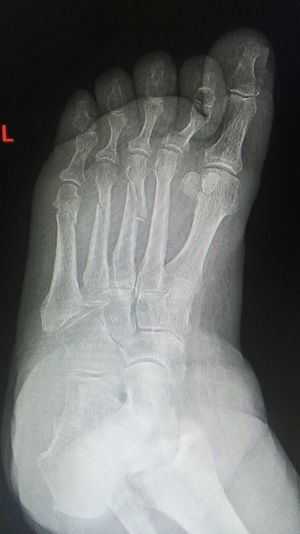

Fractures

Metatarsus